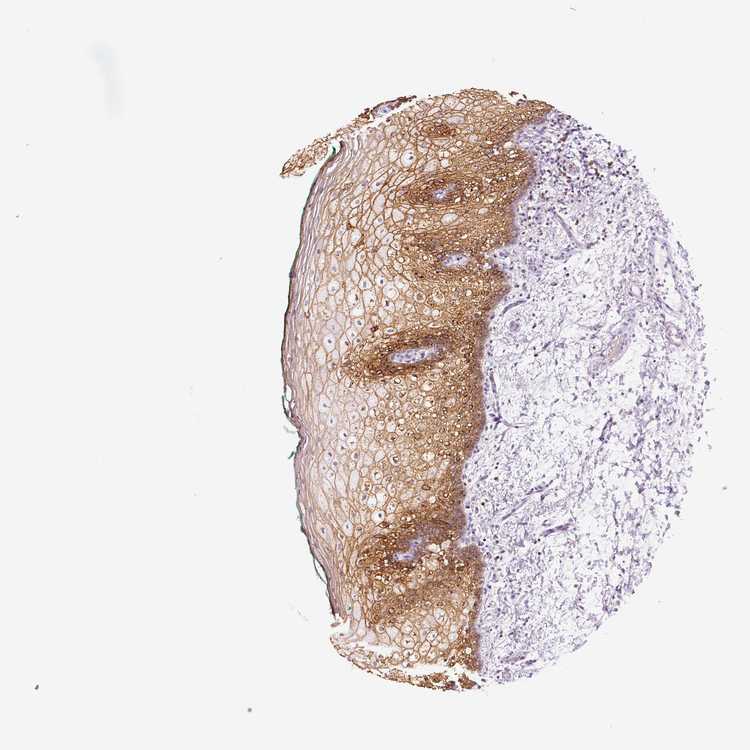

TISSUE PRIMARY DATA ORAL MUCOSA Show tissue menu

ORAL MUCOSA - Antibody stainingi

Antibody staining in the annotated cell types in the current human tissue is reported as not detected, low, medium, or high, based on conventional immunohistochemistry profiling in selected tissues. This score is based on the combination of the staining intensity and fraction of stained cells.

Each image is clickable and will lead to virtual microscopy that enables deeper exploration of all samples and also displays staining intensity scores, fraction scores and subcellular localization as well as patient and tissue information for each sample.

Antibody HPA014924

Squamous epithelial cells High